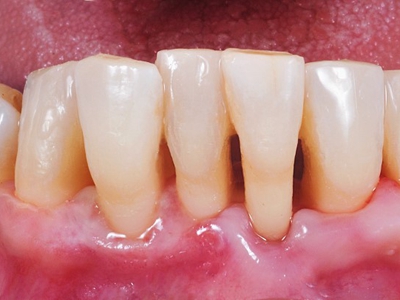

牙龈退缩上排多颗牙的牙根暴露图

牙龈退缩导致上排多颗牙齿的牙龈回缩,部分牙根暴露在外,伴有牙齿松动、口臭等症状,是由于牙周炎、局部受力过大等因素导致。